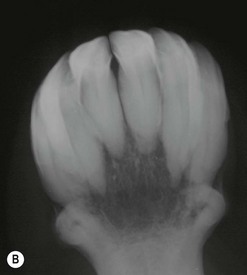

Recently, an uncommon disorder of incisor and canine teeth of aged horses, causing periodontitis, with resorptive or proliferative changes of the calcified dental tissue has been described by Klugh,80 Baratt,81 Caldwell,82 and Kreutzer et al.83 A pathological study of this disorder by Staszyk et al84 resulted in the disease being termed equine odontoclastic tooth resorption and hypercementosis (EOTRH). No plausible etiopathogenesis for this apparent immune-mediated syndrome has been described. The study by Staszyk et al84 found the disorder to primarily affect the intra-alveolar aspect of the teeth and showed the presence of odontoclastic cells in affected teeth by using tartar resistant acid phosphatase staining. These odontoclastic cells cause resorptive lesions extending into cementum, enamel, dentin, and even into pulp, causing marked loss of normal architecture in some teeth. In several areas, the resorbed areas and unaffected dental surfaces had irregular cementum deposition by cells of the periodontal ligament that led to hypercementosis in some areas (Figs 10.43 & 10.44).84 The pulp chambers of some affected teeth had irregular cementum deposition over tertiary dentin lining the chambers. This disorder shares many features with similar dental syndromes described in people85,86 and cats,87,88 but in many affected horses, a massive proliferative hypercementosis of all incisors is the main feature,89 in contrast with the more destructive syndrome observed in human and feline teeth.

Fig. 10.43 (A) The incisors of this horse have extensive cemental deposition subgingivally, and some have sinus tracts (arrow) caused by EOTRH.

image

(B) Radiograph of incisors of a 17-year-old pony that had marked gingival swelling without any sinus tracts, which shows very extensive hypercementosis of the reserve crowns of all incisors, with minimal destructive changes apparent.

Fig. 10.44 (A) Toluidine blue-stained decalcified transverse section of the mid-tooth region of 103 of horse 5. Irregular cementum (irC) fills a deep resorptive lesion that extends into normal cementum (nC) and dentin (D). The border of the irregular cementum (irC) is marked by a reversal line (open arrowheads). Wavy incremental lines (black arrow heads) indicate irregular but phasic growth. This irregular cementum contains a large vascular channel (vc). (B) Subsequent serial section of above tooth stained with Picrosirius red showing concentric deposition of intrinsic collagen fibers around the vascular channel (vc). There is parallel arrangement of the extrinsic collagen fiber bundles (white arrow heads) within the normal cementum (nC). (C) Toluidine blue-stained decalcified transverse section of the mid-tooth region of 101 of horse 4. Irregular cementum (irC) deposited in a resorptive lesion. (Inset) The white arrow indicates an ongoing resorption process at the dentinal surface. igt: inflamed granulation tissue. (D) TRAP stained decalcified transverse mid-tooth section of a 101 of horse 4, showing TRAP-positive, multinucleated odontoclasts (Oc) lying in a Howship’s lacuna at the dentinal surface (D). Mononucleates, precursors of odontoclasts (arrows) are located at a short distance behind the resorption surface.

(Reproduced from Staszyk et al84 with permission of The Veterinary Journal.)